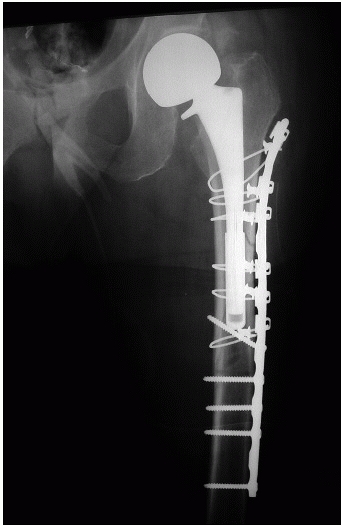

implant (Vancouver Types B2 and B3), revision of the femoral component

is typically recommended (Fig. 21-9). This strategy addresses

both the loose component and the fracture and provides intramedullary

stability by virtue of long femoral stems used for revision. Fracture

fixation with a lateral plate or reconstitution of bone stock with

allograft strut or sometimes a combination of both plates and struts

are utilized in addition to femoral component revision. In more severe

cases of bone loss, an allograft prosthesis composite, impaction bone

grafting technique, or proximal femoral replacement may be considered.80,106

selection of the appropriate uncemented reconstruction. These include

the endosteal diameter and morphology of the distal fragment. If the

distal fragment demonstrates parallel endosteal cortices with 5 cm or

more of tubular diaphysis (usually with a diameter of less than 18 mm),

then extensively coated uncemented long stem prosthesis with or without

lateral plate augmentation is appropriate (see Fig. 21-9).

![]() |

|

FIGURE 21-9 Treatment of a periprosthetic femoral shaft fracture (A) with a porus-coated long stem prosthesis with an adjunctive lateral plate that spanned the entire remaining femur (B).